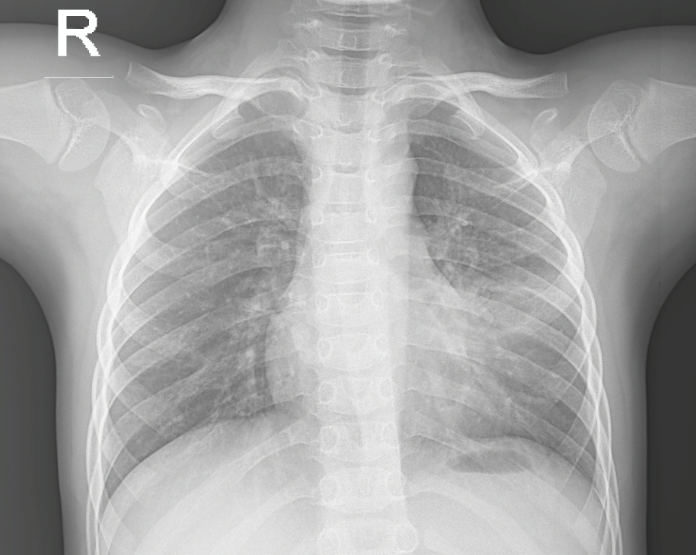

Hình ảnh Xquang BN viêm phổi thùy

Hình ảnh Xquang BN viêm phổi thùy